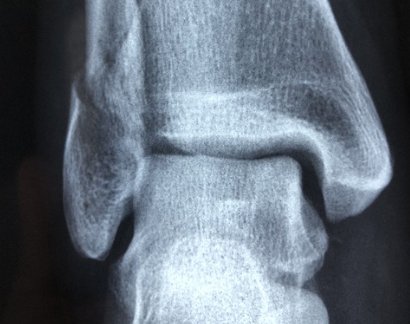

4) 골절 및 골관절염

발목 뼈의 골절이나 관절염도 통증을 유발하는 주요 원인 중 하나입니다. 골절의 경우 외부 충격으로 인해 발생하며, 심한 경우 수술적 치료가 필요할 수도 있습니다. 골관절염은 노화로 인해 연골이 닳으면서 발생하며, 만성적인 발목 통증과 부종을 동반할 수 있습니다.

치료방법:

- 골절의 경우 X-ray 촬영 후 깁스나 수술적 치료를 진행합니다.